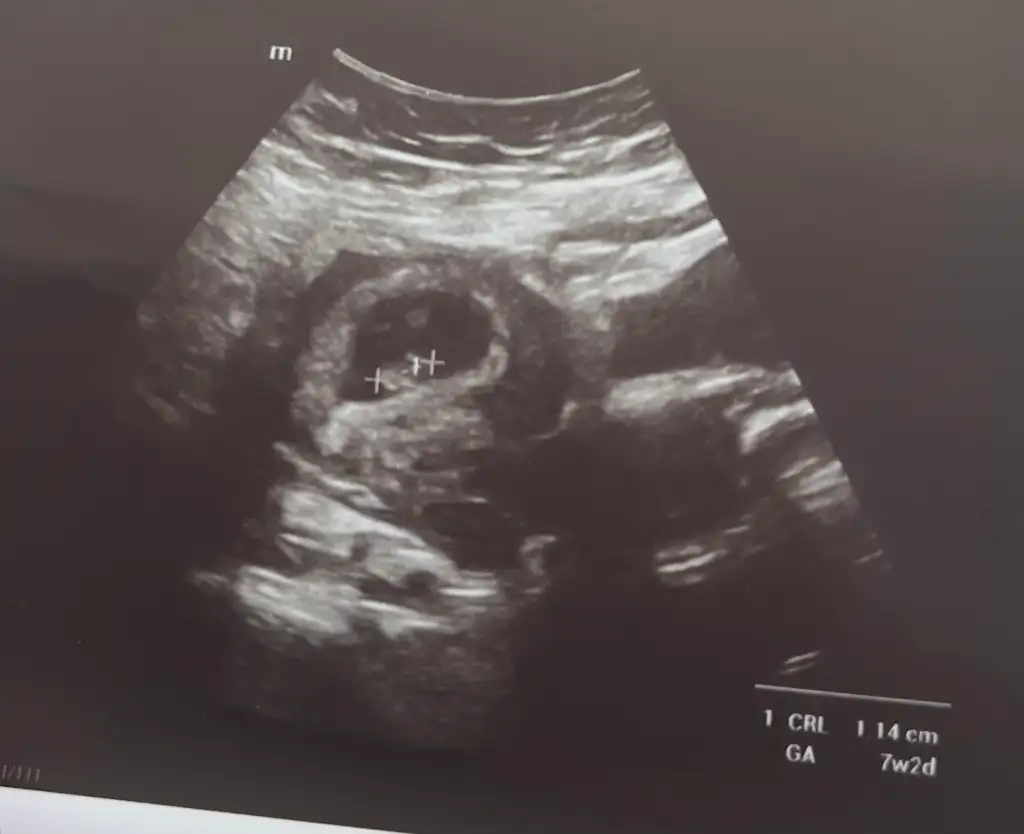

Evet erkek gibi. Yuvarlak olursa kız uzun oval fasulye olursa erkek diyorlar.Bak bakalımultrason görüntüsü 8+3